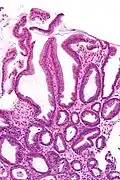

Micrograph of a reactive gastropathy. H&E stain.

Reactive gastropathy, is characterized histologically by:[2]

- Foveolar hyperplasia (black arrow), as a tortuosity in the "neck" region of the gastric glands.

- Scant or minimal inflammatory cells (white arrow), i.e. lack of large numbers of neutrophils and plasma cells..

- Smooth muscle hyperplasia in the lamina propria (in black oval).

The diagnosis is by examination of tissue, e.g. a stomach biopsy.